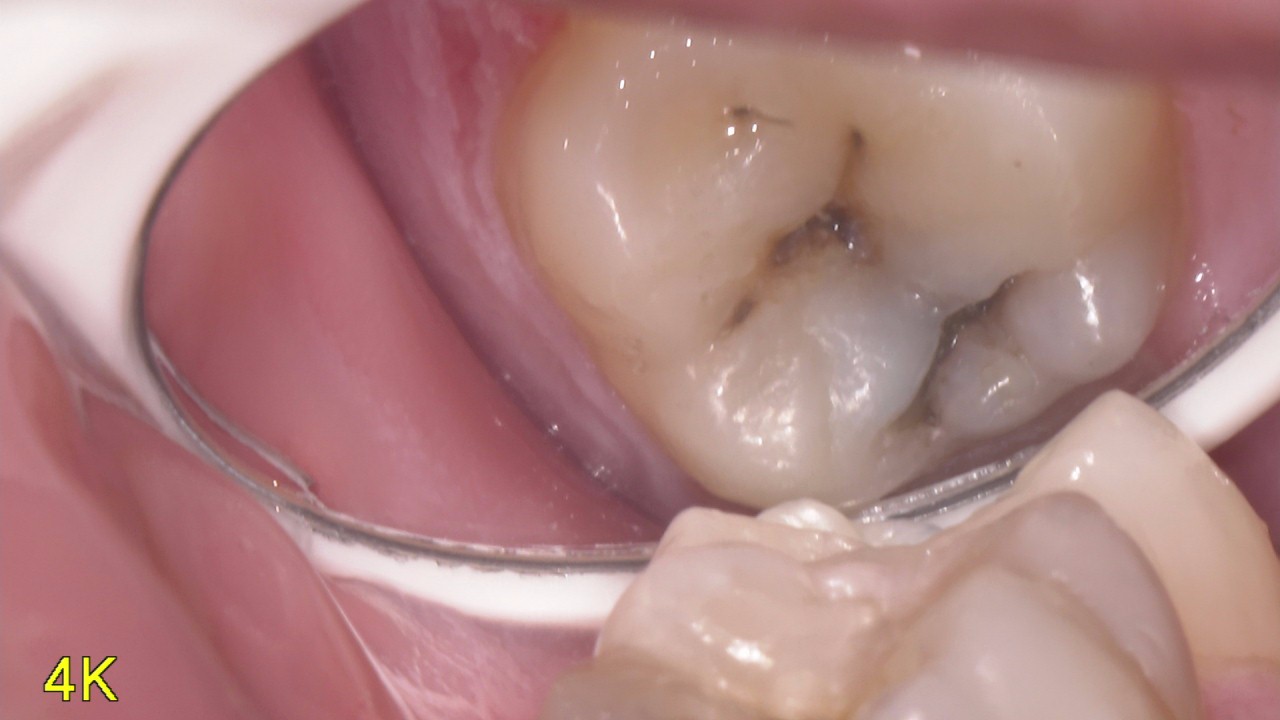

虫歯の削り方

虫歯ってどう削ってるかイメージつきますか? 削りとる器具としていろいろなものがありますが基本的には回転切削器具といわれている道具で取り切っていきます。 トンネルほったりするのとほぼ同じ機構のものです。 今回は虫歯をとって […]